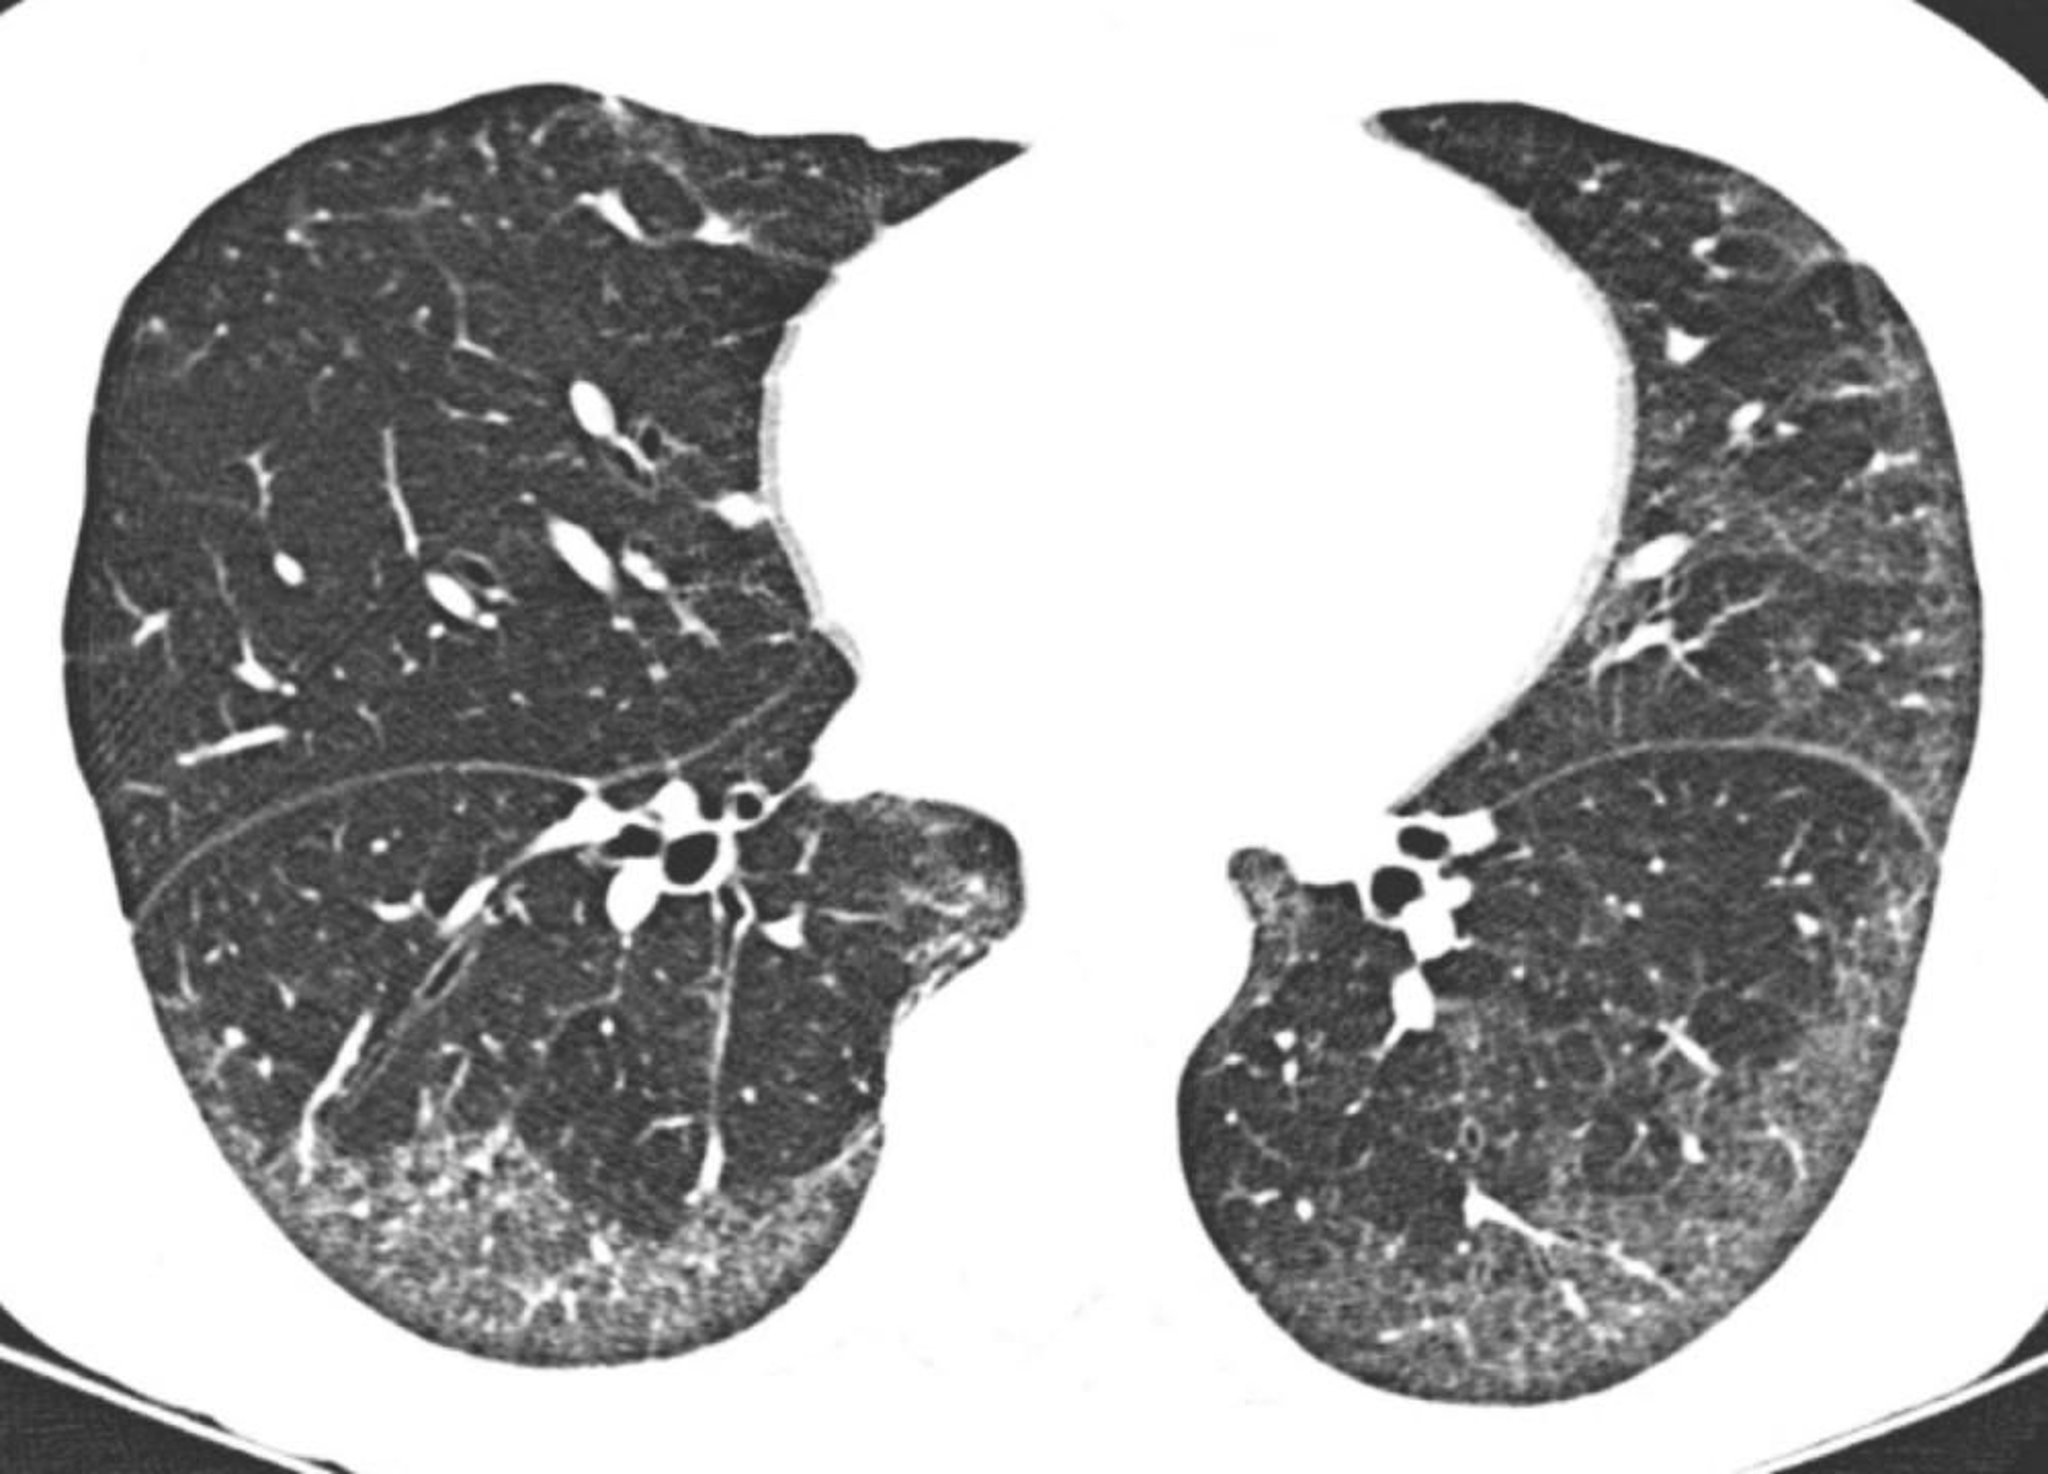

Pneumonie interstitielle idiopathique non spécifique

La TDM à haute résolution montre des opacités en verre dépoli prédominantes en sous-pleural et basilaire. L'épargne relative du poumon directement sous les surfaces pleurales est typique de la pneumonie interstitielle non spécifique.

Image courtoisie de Harold R. Collard, MD.